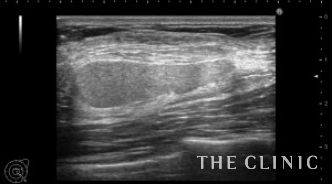

さらに1ヵ月経過後のエコーです。

黒いオイル成分が増えてきましたので、太めの注射針で穿刺吸引しました。

除去した脂肪です。

豊胸後間もない時期のしこりの性状は時間の経過とともに変化する場合もあります。